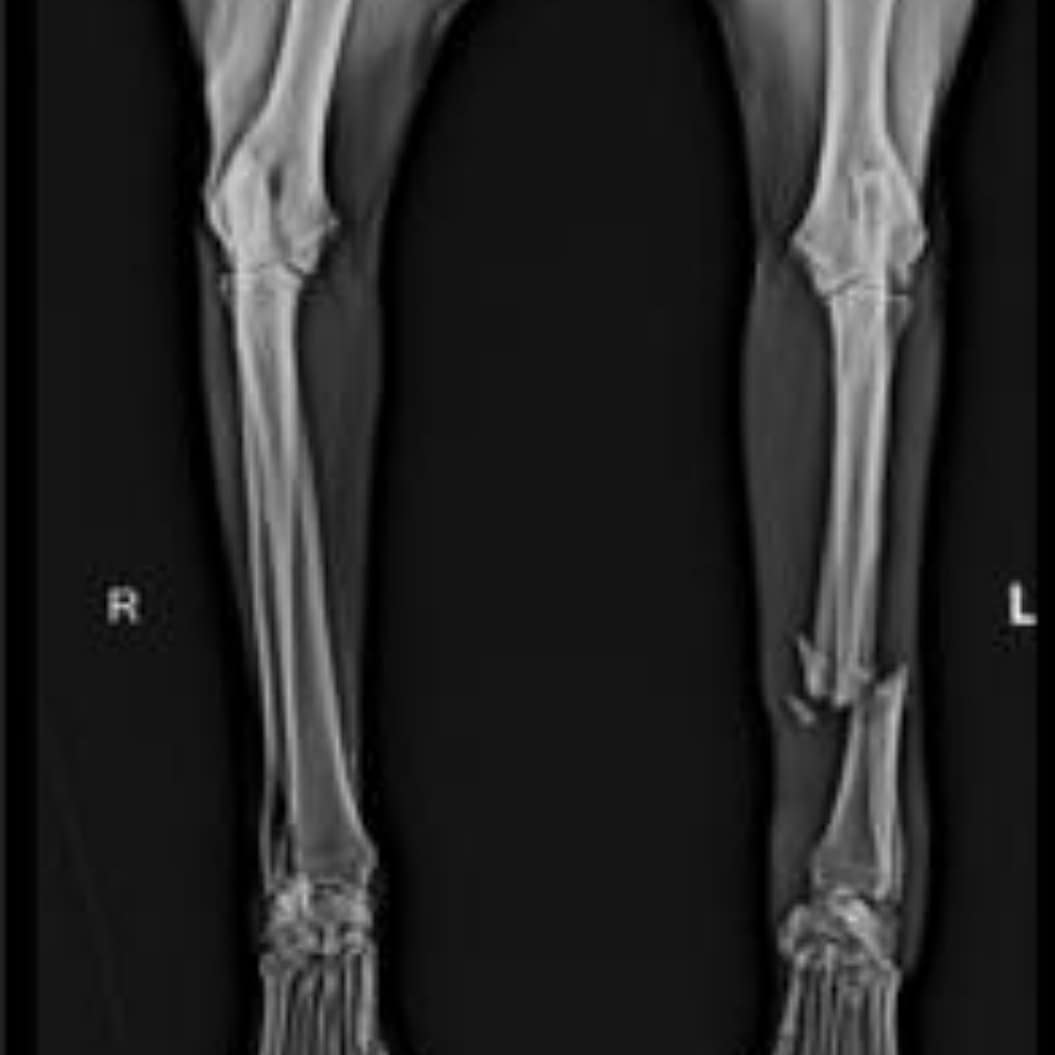

Here is her Xray and she making this appeal from her enclosure in a plaster π